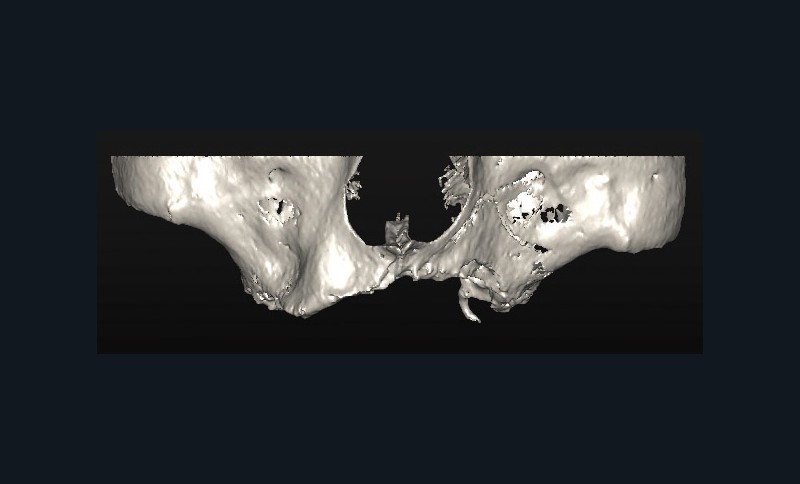

Un Dentascan® permet d’évaluer le volume osseux disponible pour une réhabilitation implanto-portée en complément de la radio panoramique de première intention. Cet examen confirme l’atrophie osseuse maxillaire (fig. 1 et 2).

En conséquence, une solution implantaire passe nécessairement par une reconstruction osseuse préalable. Une sur-élévation bilatérale des planchers sinusiens est réalisée avec un abord latéral. Les comblements des zones sous-sinusiennes sont effectués au moyen d’os allogénique (Maxgraft®) mélangé à un coagulum veineux prélevé en début d’intervention puis recouvert d’une membrane de collagène Bio-gide® et de PRF’s. La prothèse totale est évidée et rebasée périodiquement avec une résine souple.